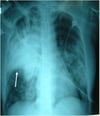

Многодолевая пневмония

Поражение правой верхней, средней и нижней долей легкого у 64-летнего мужчины с пневмококковой пневмонией.

У таких интубированных пациентов наблюдаются множественные двусторонние инфильтраты, наиболее заметные в правой верхней доле. Стрелка указывает на правую горизонтальную щель.